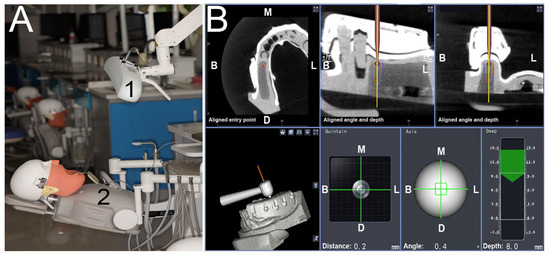

Calibration In Dynamic Navigation Surgery In Implamt

Browse our specialized Calibration In Dynamic Navigation Surgery In Implamt portfolio with numerous expertly curated photographs. optimized for both digital and print applications across multiple platforms. providing reliable visual resources for business and academic use. Each Calibration In Dynamic Navigation Surgery In Implamt image is carefully selected for superior visual impact and professional quality. Perfect for marketing materials, corporate presentations, advertising campaigns, and professional publications All Calibration In Dynamic Navigation Surgery In Implamt images are available in high resolution with professional-grade quality, optimized for both digital and print applications, and include comprehensive metadata for easy organization and usage. Our Calibration In Dynamic Navigation Surgery In Implamt collection provides reliable visual resources for business presentations and marketing materials. Whether for commercial projects or personal use, our Calibration In Dynamic Navigation Surgery In Implamt collection delivers consistent excellence. The Calibration In Dynamic Navigation Surgery In Implamt archive serves professionals, educators, and creatives across diverse industries. Regular updates keep the Calibration In Dynamic Navigation Surgery In Implamt collection current with contemporary trends and styles. Advanced search capabilities make finding the perfect Calibration In Dynamic Navigation Surgery In Implamt image effortless and efficient. Multiple resolution options ensure optimal performance across different platforms and applications.